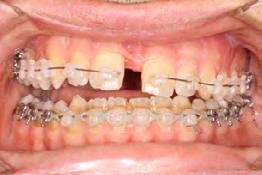

Palatal mini-implants were placed by a periodontist, followed by placement of the rapid palatal expander (RPE) and bonding of the mandibular arch with self-ligating Damon clear braces. Patient had SARPE surgery performed by the oral surgeon three weeks later (Figure 2), and the expander was turned once a day for three weeks (Figure 3). The maxillary arch was then bonded. Both archwires were incremen-

tally upgraded to an 18 x 25 NiTi wire, and the patient was placed on vertical elastics on the right side. With enough space for the tongue, the lateral open bite began to close.

Approximately six months after insertion of the RPE, digital scans were taken for SureSmile custom wires and the patient was scheduled for the SFOT procedure with the oral surgeon. The RPE was removed, SureSmile wires inserted and segmental corticotomies performed, immediately followed by further vertical elastics on the right side (Figure